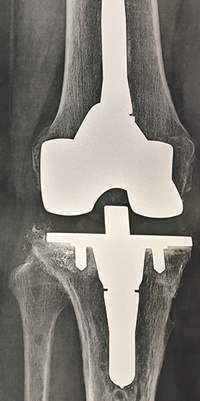

Exemple de reprise de prothèse

Ci-dessous, vous pouvez voir la radio d'une prothèse partielle interne, 12 ans après la pose initiale, avec enfoncement de la pièce tibiale dans le tibia (flèche rouge) et la radio de la prothèse de reprise avec une longue tige.